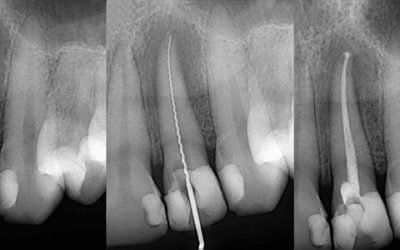

Voraussetzung für eine belastbare Diagnose ist die Anfertigung einer Röntgenaufnahme von Zähnen und Kieferknochen,. Im Mittelpunkt einer endodontischen Therapie liegt die Behandlung des Wurzelkanals. Der Zahnarzt benutzt spezielle feine Instrumente und Feilen, mit denen er den Wurzelkanal aufbereitet und erweitert. Dies erfolgt in mehreren Arbeitsgängen mit präzisen Auf- und Abwärtsbewegungen der rotierenden Instrumente, ist sehr zeitaufwändig und erfordert ein gutes Fingerspitzengefühl des Zahnarztes. Denn die Wurzelkanäle sind nicht immer gerade angelegt, sondern können auch gebogen sein. Dies erschwert die Aufbereitung des Wurzelkanals. Röntgenbilder geben Aufschluss über Länge und Form der einzelnen Wurzelkanäle und das Ausmaß der Entzündung. Anschließend muss der präparierte Kanal gründlich mit desinfizierenden Lösungen gespült und durchgängig gemacht werden, um entzündetes Gewebe und Bakterien zu entfernen. Zum Abschluss trocknet der Zahnarzt den Kanal mit feinen Papierspitzen und versiegelt ihn mit speziellen Füllmaterialien, wie z.B. Guttapercha-stiften und Pasten oder Zement, um ein erneutes Eindringen von Bakterien zu verhindern.